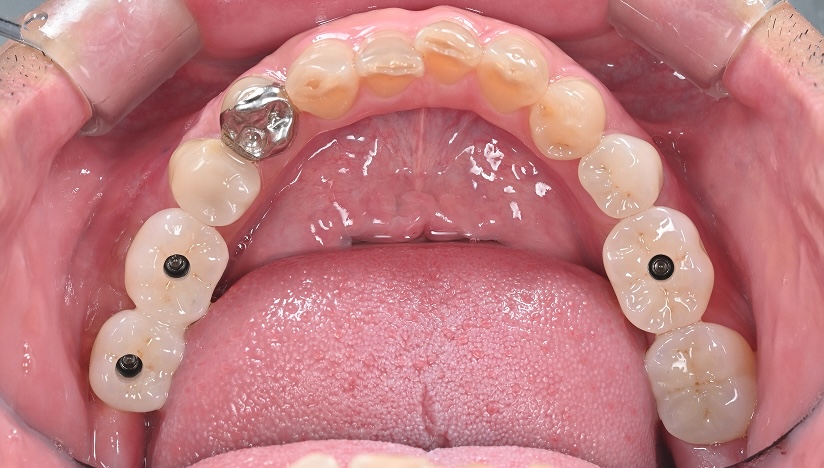

切開をせずに

インプラントをした症例

主訴

前歯がグラグラしてきた

診断

臼歯部支持の喪失に伴う前歯部への過大な咬合負担

および上顎洞底の高度な歯槽骨吸収

治療方針

前歯部の動揺は、臼歯部での垂直的な咬合支持の欠如により、前歯部へ過大な負担が集中していることが原因と考えられた。

臼歯部には既存補綴装置が装着されていたが、十分な咬合支持が得られていなかったため、インプラントによる咬合再構築を計画した。

また、上顎洞底の骨吸収が高度であったため、インプラント埋入に先立ち両側サイナスリフトを行い、十分な骨量を確保した上でインプラント埋入を行う方針とした。

患者は外科的侵襲に対する不安が強かったため、最終的にはフラップレスでのインプラント埋入を計画した。

治療内容

両側サイナスリフト

フラップレスインプラント埋入(4本)

治療期間

約6〜8ヶ月(骨成熟期間を含む)

治療費用

1,600,000

結果

十分な骨造成が得られ、フラップレスによる低侵襲なインプラント埋入が可能となった。術後経過も良好で、咬合支持の再構築による機能回復が得られている。

治療の

リスク

シュナイダー膜の穿孔、上顎洞炎、骨量不足により追加処置が必要となる可能性

考察

高度な骨吸収症例では、インプラント埋入と同時に骨造成を行う方法も選択肢となる。 本症例では骨量の確実な獲得と安全性を優先し、サイナスリフトを先行する段階的治療を選択した。

その結果、十分な骨量が確保され、最終的にフラップレスによる低侵襲なインプラント埋入が可能となった。外科的侵襲を可能な限り抑えながら、安全性と長期的安定性を両立した治療につながった症例である。